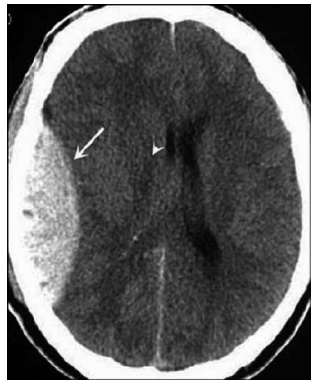

Homem de 45 anos foi atendido na emergência após

sofrer uma queda de altura. A tomografia de crânio encontra-se a seguir.

Com base nesses achados, qual é o diagnóstico mais provável?